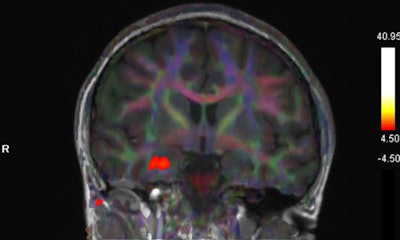

Fused BOLD and fractional anisotropy map on coronal T1-weighted image shows activation of the right uncus/piriform cortex with intact, symmetric architecture of surrounding white-matter tracts.The patient in the case report experienced taste and smell dysfunction for three months and had been referred to a neurology clinic, where she had a normal examination. Clinicians performed a task-based functional MRI study that involved exposure to smells and the generation of BOLD activation maps. Activation was not seen in the orbitofrontal cortex, while there was a strong BOLD signal in the right uncus/piriform cortex, they reported.

"The utility of fMRI in patients with COVID-19 is not well established, and to our knowledge this is the first published report using fMRI in a patient with persistent cacosmia and cacogeusia after COVID-19 infection," they wrote. "Given these findings, we could suggest central olfactory pathway impairment, mainly involving OFC, may be involved in the underlying etiology of persistence of olfactory and gustatory symptoms in patients after COVID-19 infection."